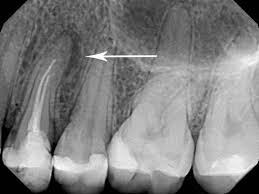

the root of the problem

the part i hate is when they take those wire things

hold them up where i can see them as they look to

see if they went far enough

makes me a little squeamish when they do that

it seems they can use lasers to stimulate the formatin of dentin

thats the natural cement stuff we make in our teeth

apparrently it stimulates stem cells in the tooth

the dentin stimulated fills up the holes where the tooth is damaged

the blood vessels remain intact with this method

with a root canal they are destroyed

no wire stuff needed